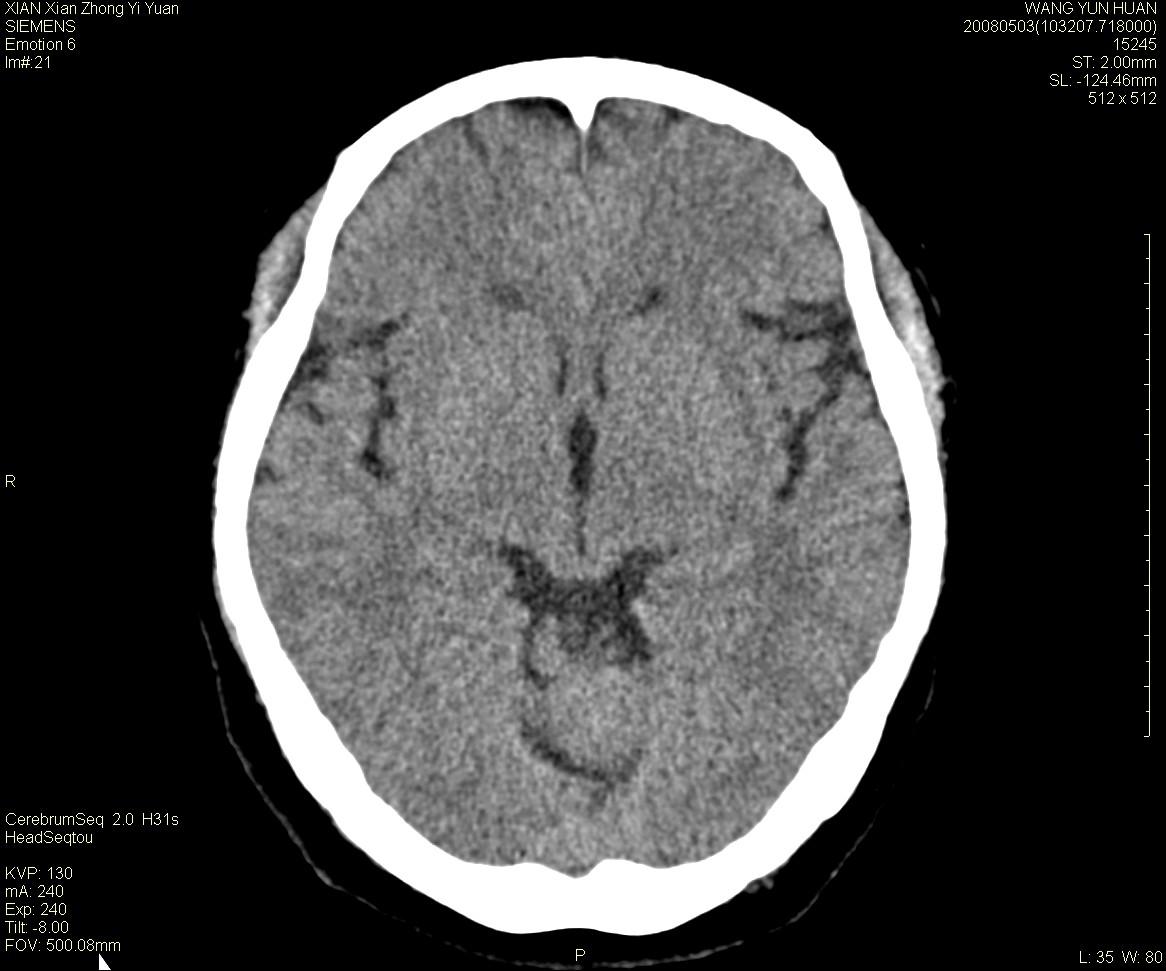

标题: CT13219:(补充强化)请会诊,患者女,60岁,头晕,大家看 [打印本页]

标题: CT13219:(补充强化)请会诊,患者女,60岁,头晕,大家看

病灶显示轻度强化,ct增加4hu左右,大家看是什么肿瘤.

强化后动脉期及延迟2分钟,五分钟图像

小脑蚓部囊型肿块,内有实性结节及钙化点。增强后囊壁及结节轻度强化。

考虑蚓部星形细胞瘤(ⅱ级可能性大)。

小脑蚓部肿块,周围无明显占位效应及水肿带,增强轻度强化,考虑低分级星形细胞瘤。